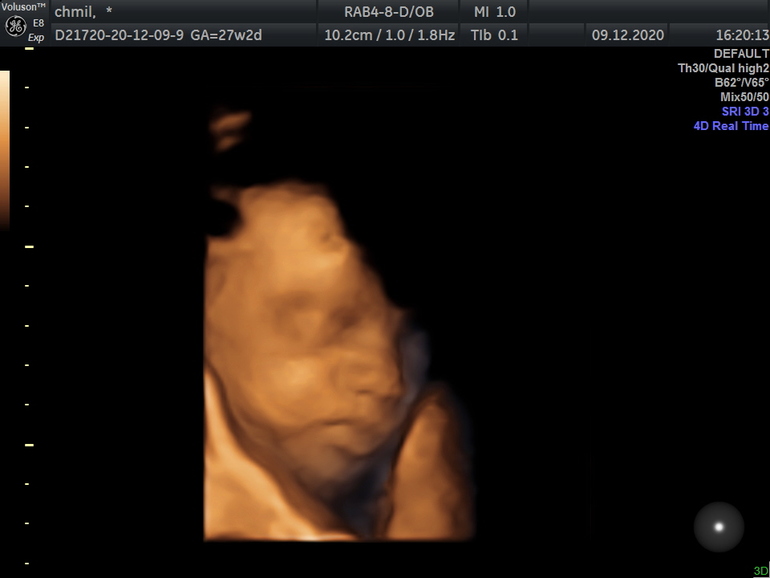

Короче поехали мы на узи, врач была просто душка, очень ласково разговаривала с малышом, умилялась вместе с нами, всё-всё коммментировала и весь процесс можно было наблюдать на большом экране. Ещё показала детеныша в 4д и скинула фотки на флешку😍! Правда он опять сосал палец и почти все время закрывал руками лицо, но потом всё же сделал одолжение и разрешил посмотреть на него как следует пару минут))

Здесь ⬇️ скривился, видимо обиделся, что смеялась над его сплющенным носом))

Пришли к выводу, что когда он спокоен - похож на меня, а когда корчит морды и недоволен - вылитый муж 🤣. Для сравнения, вот моё первое фото: